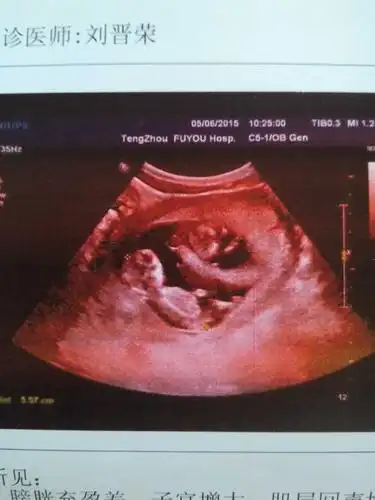

[试管婴儿]b超啦妥妥的双胞胎哦~~~感谢

7周 6,b超查出双胞胎!

第一次b超检查结果出来啦,是双胎,好开心啊,医生说看单子一切正常

b超归来,有双胞胎的宝妈吗?